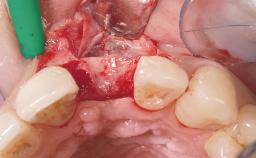

A 77-year-old male patient was referred for the management of frequent and repeated acrylic fracture of his existing mandibular fixed full-arch implant-supported metal/acrylic prosthesis. He also complained about softtissue soreness and the lack of retention and stability of his maxillary removable partial metal/acrylic prosthesis. Both prostheses had been delivered two years previously as part of his full-mouth rehabilitation (caries, tooth wear, tooth fracture). His medical history revealed high blood pressure, controlled with the use of antihypertensive medication.